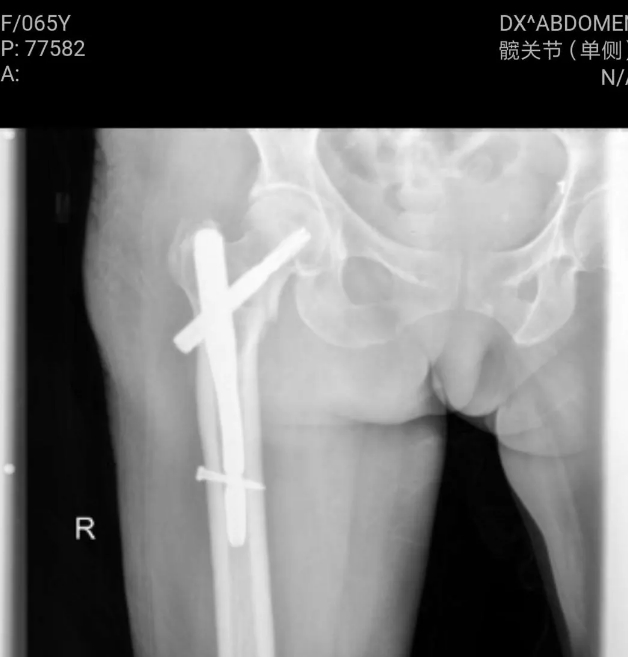

骨科一组擅长创伤骨科、显微外科及关节病阶梯化治疗,疫情期间独立完成医院骨科首例股骨近端骨折髓内钉内固定术,填补我院技术空白。